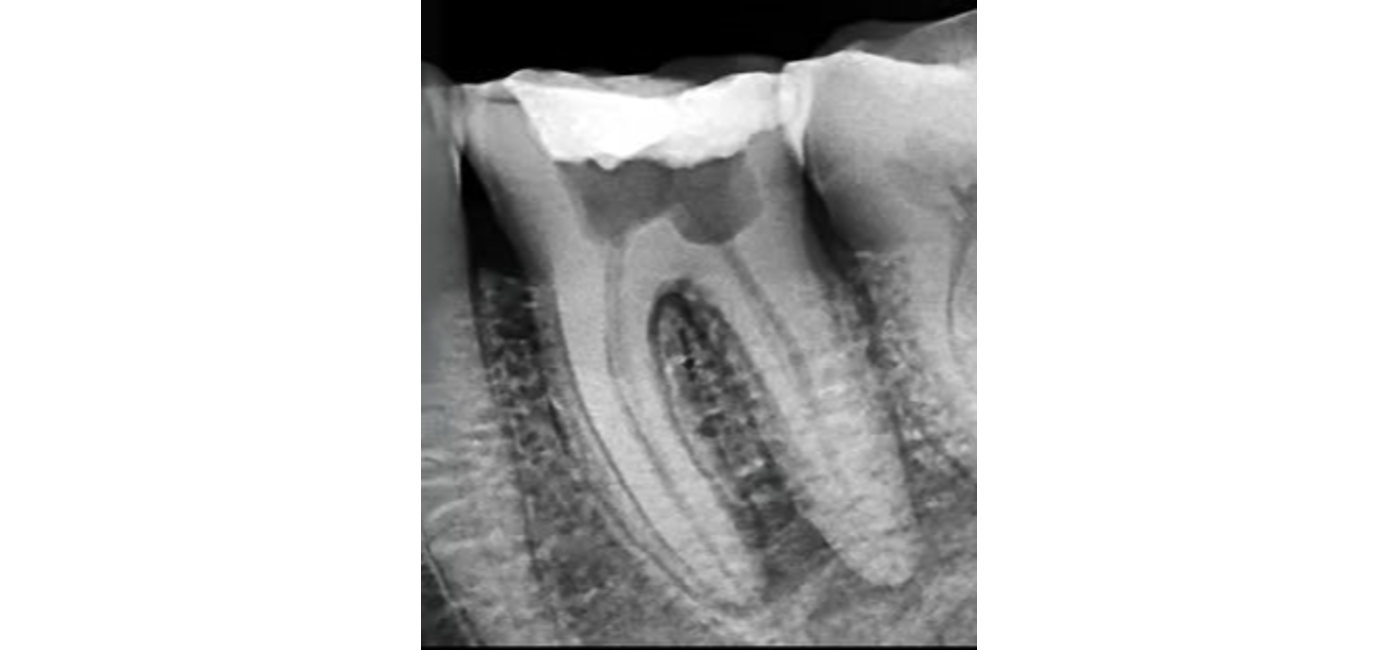

El procedimiento se realiza bajo anestesia local y se lleva a cabo en varias fases. Primero, el odontólogo o endodoncista accede a la cámara pulpar del diente para extraer la pulpa dañada. Luego, se limpian y desinfectan cuidadosamente los conductos radiculares con instrumentos especializados y soluciones antimicrobianas. Posteriormente, estos conductos se rellenan con un material biocompatible, generalmente gutapercha, que sella el interior del diente. Finalmente, se coloca una restauración temporal o definitiva, como una corona, para proteger el diente y devolverle su forma y función.

Gracias a los avances tecnológicos, la endodoncia moderna se realiza con equipos rotatorios, lupas de aumento, radiografías digitales y localizadores electrónicos de ápice, lo que garantiza una mayor precisión, rapidez y confort para el paciente. En la mayoría de los casos, el tratamiento se completa en una o dos sesiones y el alivio del dolor es casi inmediato.